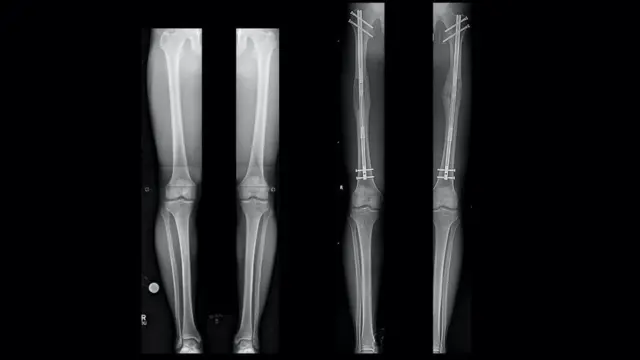

ٹانگوں کی ہڈیوں میں ایک سوراخ کیا جاتا ہے جسے پھر دو حصوں میں توڑا جاتا ہے۔ ایک دھات کا راڈ اس میں سرجیکل طور پر ڈالا جاتا ہے اور متعدد پیچوں کے ذریعہ اسے کس دیا جاتا ہے۔ پھر اس راڈ کو روزانہ آہستہ آہستہ ایک ملی میٹر تک بڑھایا جاتا ہے اور اس وقت تک بڑھایا جاتا ہے جب تک کہ سرجری کروانے والا مطلوبہ اونچائی نہ حاصل کر لے اور پھر ان کی ہڈیاں ایک ساتھ مل کر ٹھیک ہوجائیں۔

،تصویر کا ذریعہDR S. ROBERT ROZBRUCH